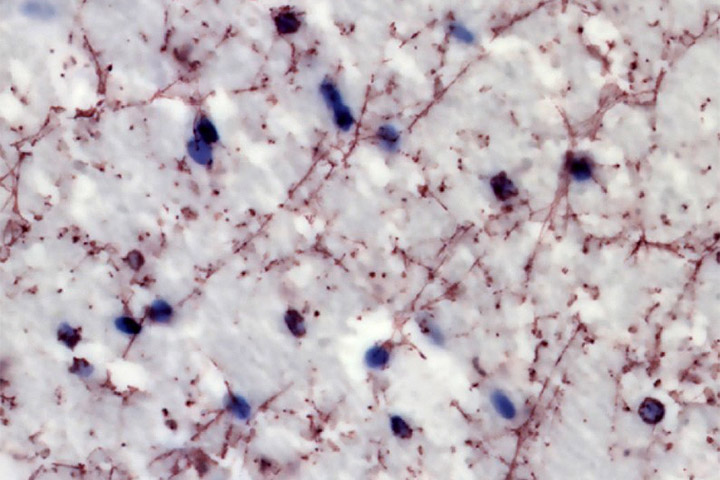

© Andry Andrianarivelo and Peter Vanhoutte—Neuroscience Paris Seine laboratory (CNRS / Sorbonne University / INSERM)

Drug addiction is a psychiatric disorder for which no pharmacological treatment with long-term efficacy currently exists. All addictive substances share the property of raising concentrations of the neurotransmitter dopamine within brain regions forming the neural reward circuit. This increase in dopamine levels results in long-lasting alteration of signal transmission that is dependent on another neurotransmitter, glutamate, which causes addictive behaviours.

Through a new study, an international team including scientists from the CNRS, INRAE, the CEA, Sorbonne University, Paris-Saclay University, the University of Bordeaux, and Université Côte d’Azur* has uncovered, in mice and humans, the molecular bases of this deleterious interplay between dopamine and glutamate. The researchers’ work shows that the inhibition of interactions between dopamine and glutamate receptors prevents pathological behaviours provoked by cocaine in mice, without altering natural reward processing. Their findings, published in Science Advances (20 October 2021), pave the way for the development of new therapeutic strategies to treat addiction, and a wider spectrum of psychiatric disorders.

Disrupting D1-NMDA or D2-NMDA receptor heteromerization prevents cocaine’s rewarding effects but preserves natural reward processing.